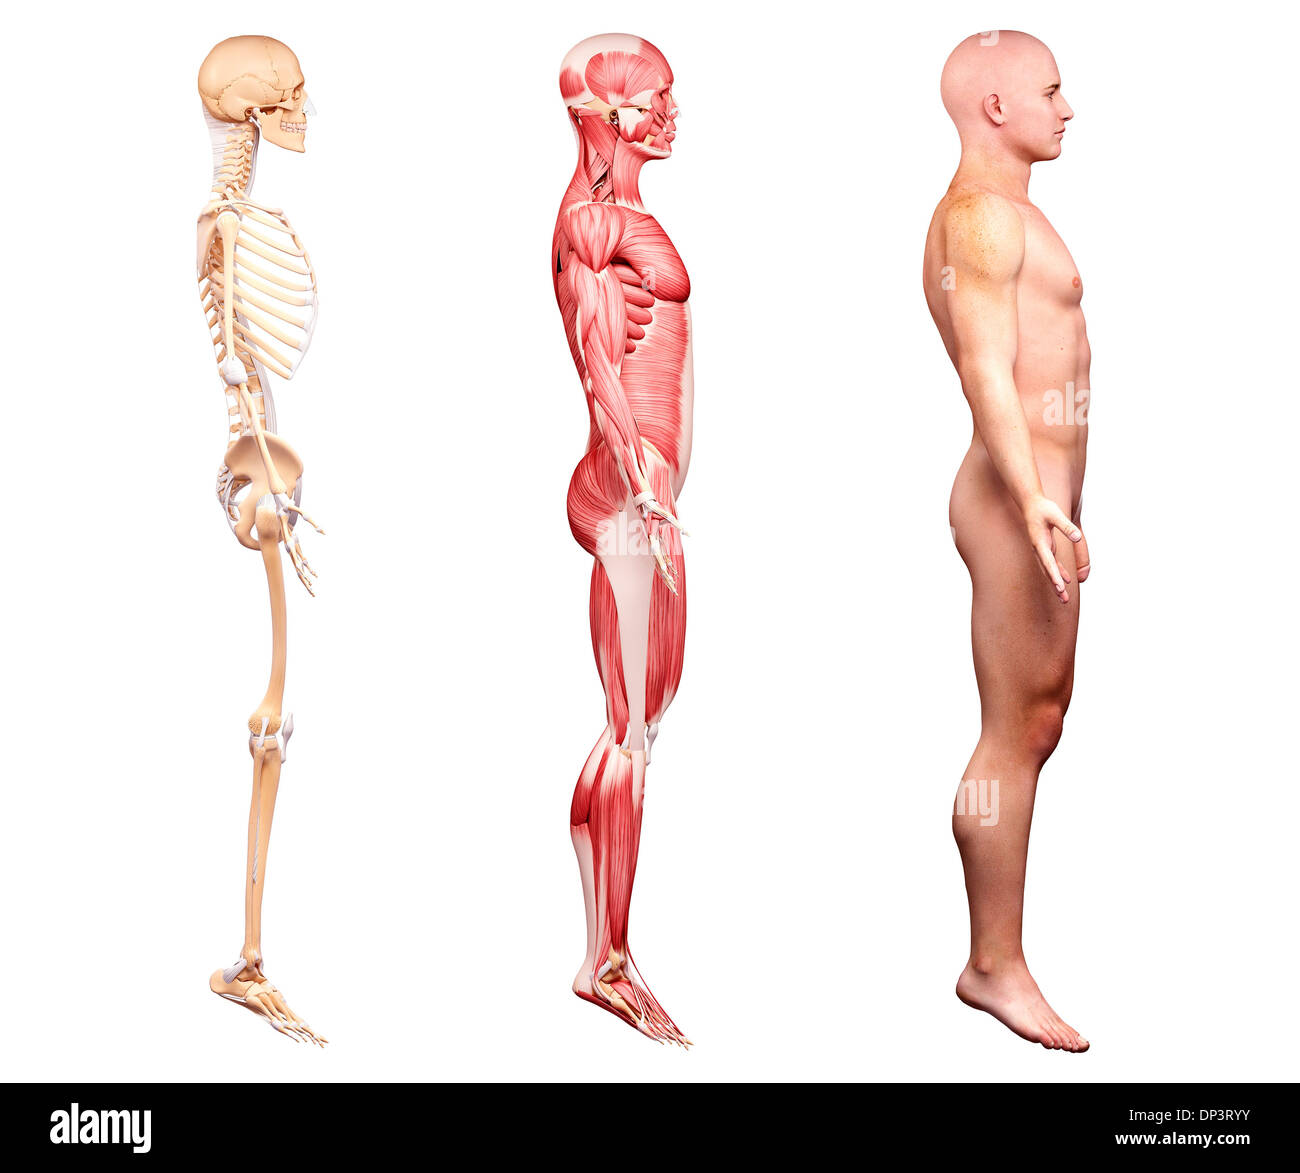

Male anatomy, artwork Banque D'Imageshttps://www.alamyimages.fr/image-license-details/?v=1https://www.alamyimages.fr/male-anatomy-artwork-image65238207.html

Male anatomy, artwork Banque D'Imageshttps://www.alamyimages.fr/image-license-details/?v=1https://www.alamyimages.fr/male-anatomy-artwork-image65238207.htmlRFDP3RYY–Male anatomy, artwork